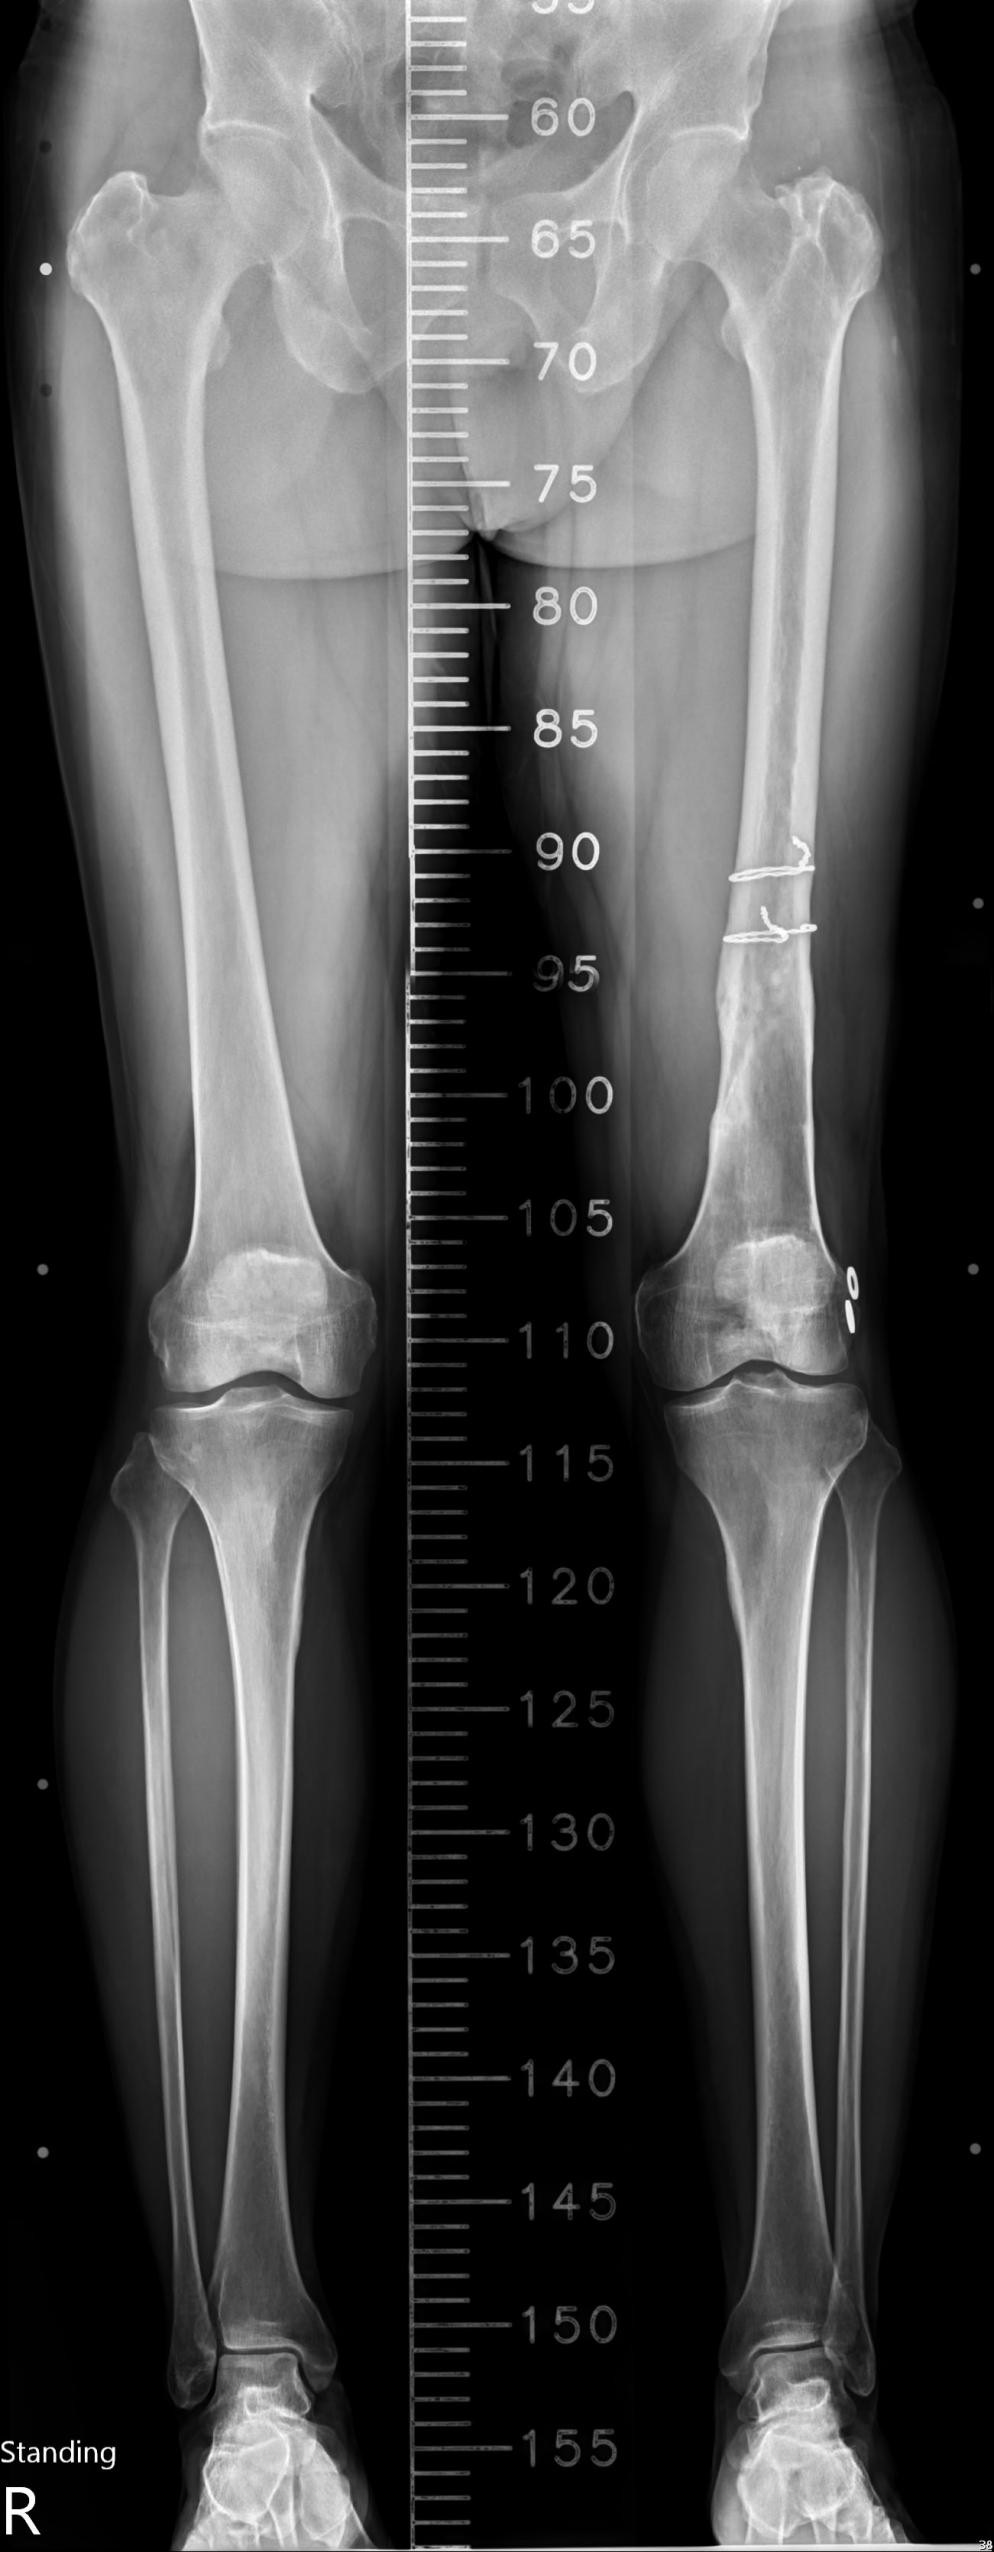

A 52-year-old male presented with right knee medial pain for 3 months, exacerbated by stair climbing and squatting, associated with popping and locking sensations. On physical examination, the range of motion (ROM) of the right knee is mildly limited by pain during flexion, medial joint line tenderness, and a positive McMurray test for the posterior horn of the medial meniscus. Gross effusion is noted, with aspiration yielding 40 cc of serous fluid containing chondral debris. Radiographs and scanography reveal no significant mechanical axis deviation, and the knee appears grossly normal on imaging. He denies any recent trauma but has a history of an old femoral fracture treated with surgical fixation and subsequent implant removal (Fig. 1).

Figure 1: Full-length frontal radiographs of both lower extremities show no significant mechanical axis deviation.